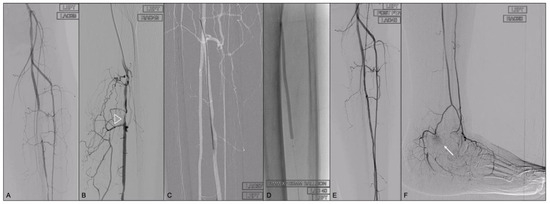

- Due to its deep location, the retrograde puncture of the PA under US guidance, as described by Mustapha et al. [31], could be challenging and complete fluoroscopic guidance via the lateral compartment was preferred in our case series.

- A gentle medial rotation of the leg is usually helpful to open the gap between the tibia and the fibula without requiring excessive obliquity of the C arm.

- The following parallax principle must be outlined: the needle should be aligned with the long axis of the road-mapped vessel. The PA can be punctured at almost any level apart from the very distal tract where the needle cannot reach the target due to bone interposition. To use an angiographic subtracted image as guidance for the puncture is preferrable when compared with fluoroscopic guidance by arterial calcifications to minimize access in calcified/more diseased segments of the PA. The use of nerve block, spinal or general anaesthesia could help in terms of movement artifact reduction.

- We found that in the vast majority of our cases, two different angiograms in two orthogonal planes and contrast injections when the needle is close to puncturing the artery, as described by Zhuang [17], are not necessary. If the needle is kept in line with the course of the PA, as assessed under fluoroscopic guidance, it will impact the target artery approximately 4–5 cm from the skin. The tactile feeling generated by the passage through the interosseous membrane means that the artery is roughly 1 cm away. We think that our simplified technique could save at least 20 mls of contrast compared to the mentioned Zhuang approach [17].

- We consider a mini-invasive sheath-less approach, using a 0.018 compatible catheter (CXI, COOK MEDICAL, Bloomington, Indiana or Navicross, Terumo, Tokyo, Japan) and a 0.018 guidewire with a stainless steel shaft (V18, Boston Scientific, Marlborough, MA or Command 018, Abbott Vascular, Santa Clara, CA, USA) as a safer approach than retrograde sheath placement [35].